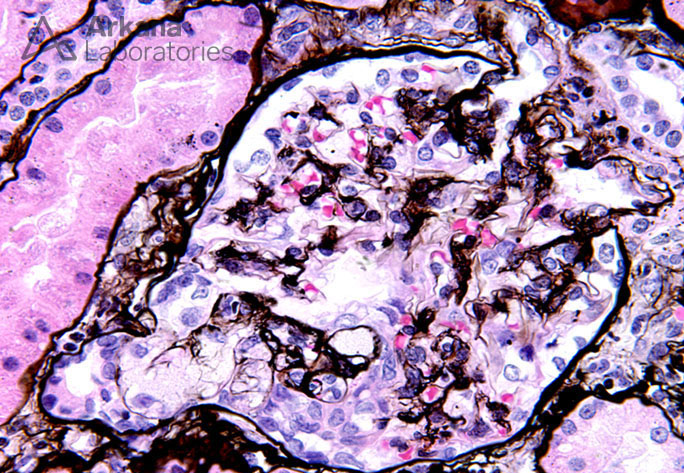

Enlarged Glomerulus with a FSGS Tip Lesion on Silver Stain